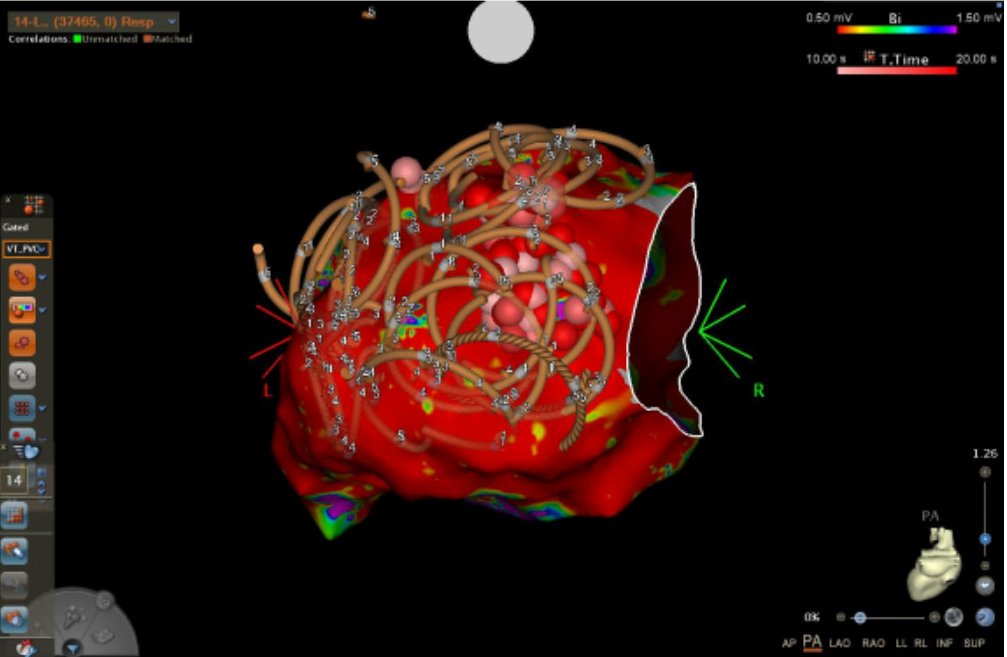

Unfortunate 33 y/o transferred for AE Fistula 6 years ago had thoracotomy, mediastinal debridement, esophageal stenting/removal. 6 yrs later presented with microreentrant flutter from the scar related to the AE infection. #Epeeps @gautamsand @narrowQRS @jskoruth @EJSMD @SergioPinski

Madhu Reddy tweet mediaMadhu Reddy tweet media

@sumitvermaep @gautamsand @narrowQRS @jskoruth @EJSMD I got a CT of chest/abdomen to reevaluate his anatomy and reviewed last UGI endoscopy from a few years ago. Some variation in anatomy due to his prior event and surgical changes. But overall looked acceptable. Did posterior wall isolation in addition to PVI with FaraPulse